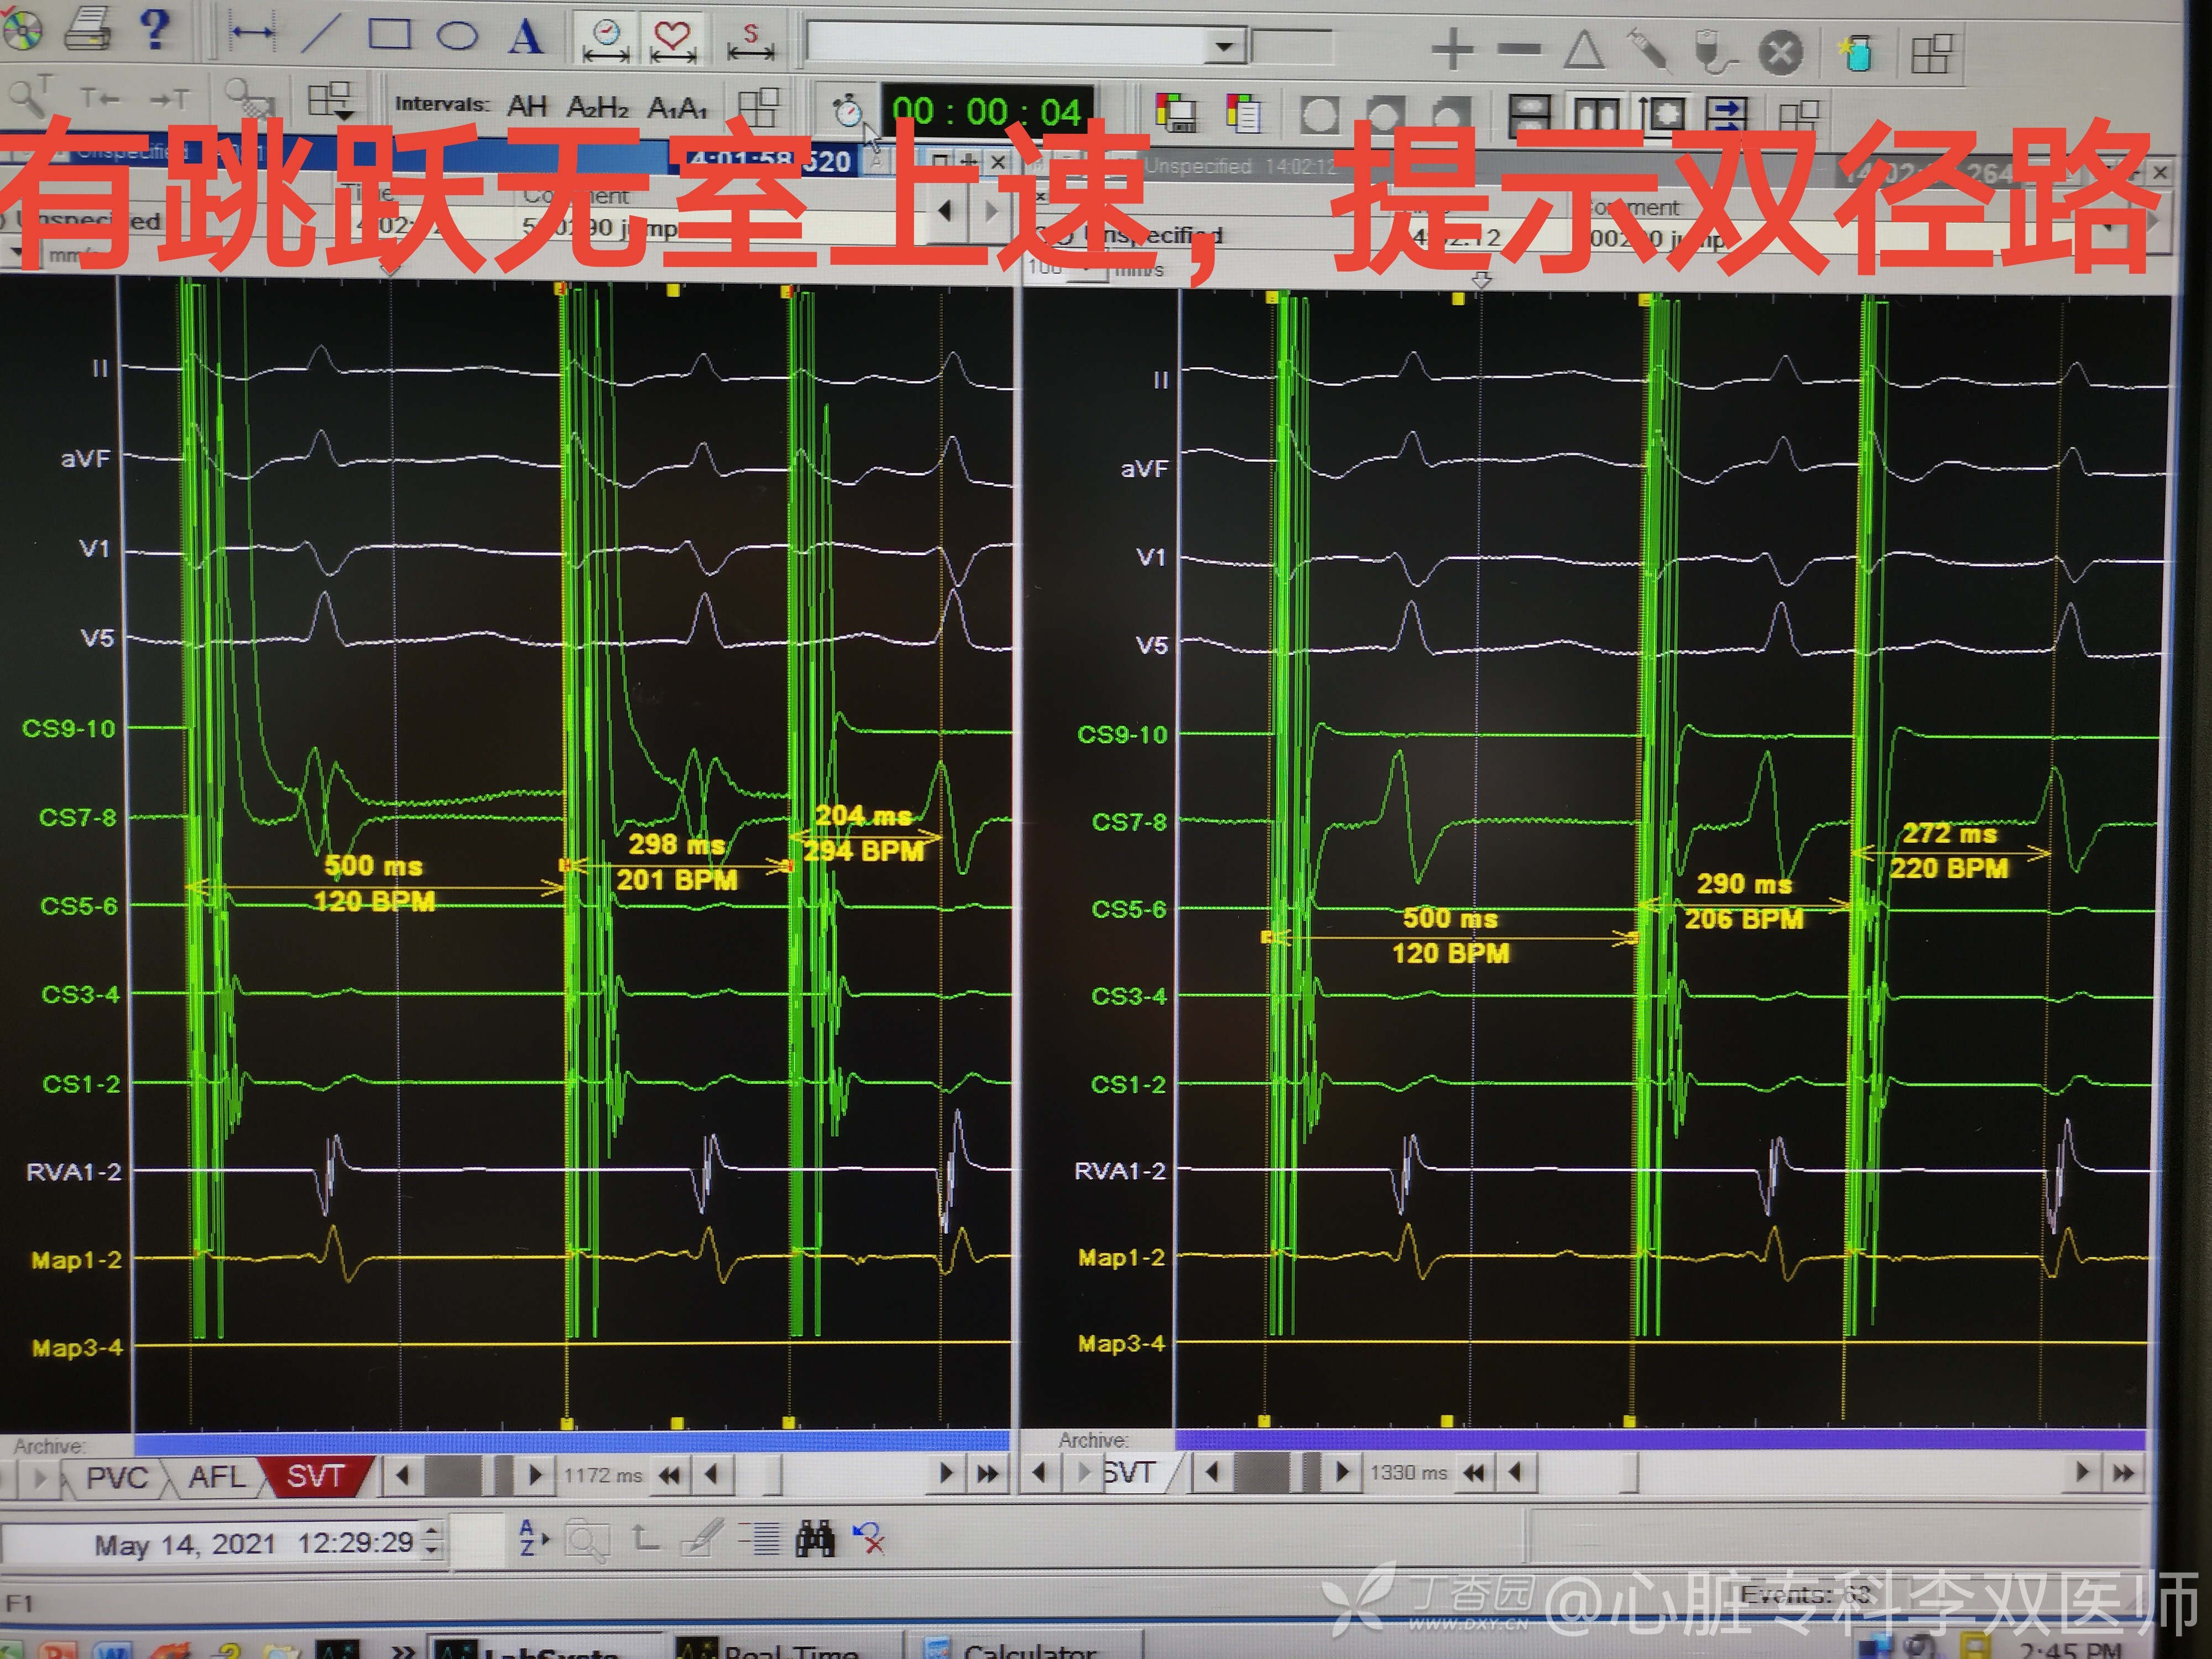

还有系统检查,果然!我们发现了同时存在“双径路”,很稳定诱发(S1S2,S1S2S3都是两次一样条件),但是没有回波,也不能诱发室上速。给了异丙肾反复刺激也是没有回波没有室上速,这种情况一般是不主张继续消融“双径路”的。